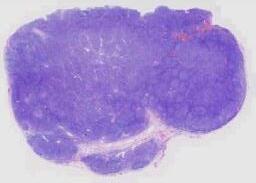

临床资料: 男,66岁,主诉:水肿、颈部淋巴结肿大,同期发现房颤。现病史:2020-05出现心悸伴颜面部、颈部、四肢水肿,尿量减少(约500ml/d),咳嗽、喘憋、活动耐量明显下降。外院完善ECG:“房颤”,颈部超声:双侧颈部淋巴结肿大。2020-06我院查:血常规:(-),肝肾功:LD365U/L,余(-);心肌酶(-);NT-proBNP1465pg/ml;感染:HBcAb(+),HBsAb(+);ECHO:LVEF69%,左房增大,心包少量积液。PET-CT示:1.左侧颈部(IV区、V区)、左侧锁骨上下、右肺门及后纵隔、腹膜后、肠系膜上多发代谢增高淋巴结(大小约0.5-1.6cm,SUVamx13.2),右心房、右心室及双侧心耳见多发代谢增高结节和肿物(大小约2.0×2.3-5.8×7.6cm,SUVamx24.6)、第2/3组小肠壁明显增厚且代谢增高异常(SUVamx17.1)。取左颈根部淋巴结送检。

大体所见: 淋巴结样组织数枚,直径0.5-2cm。